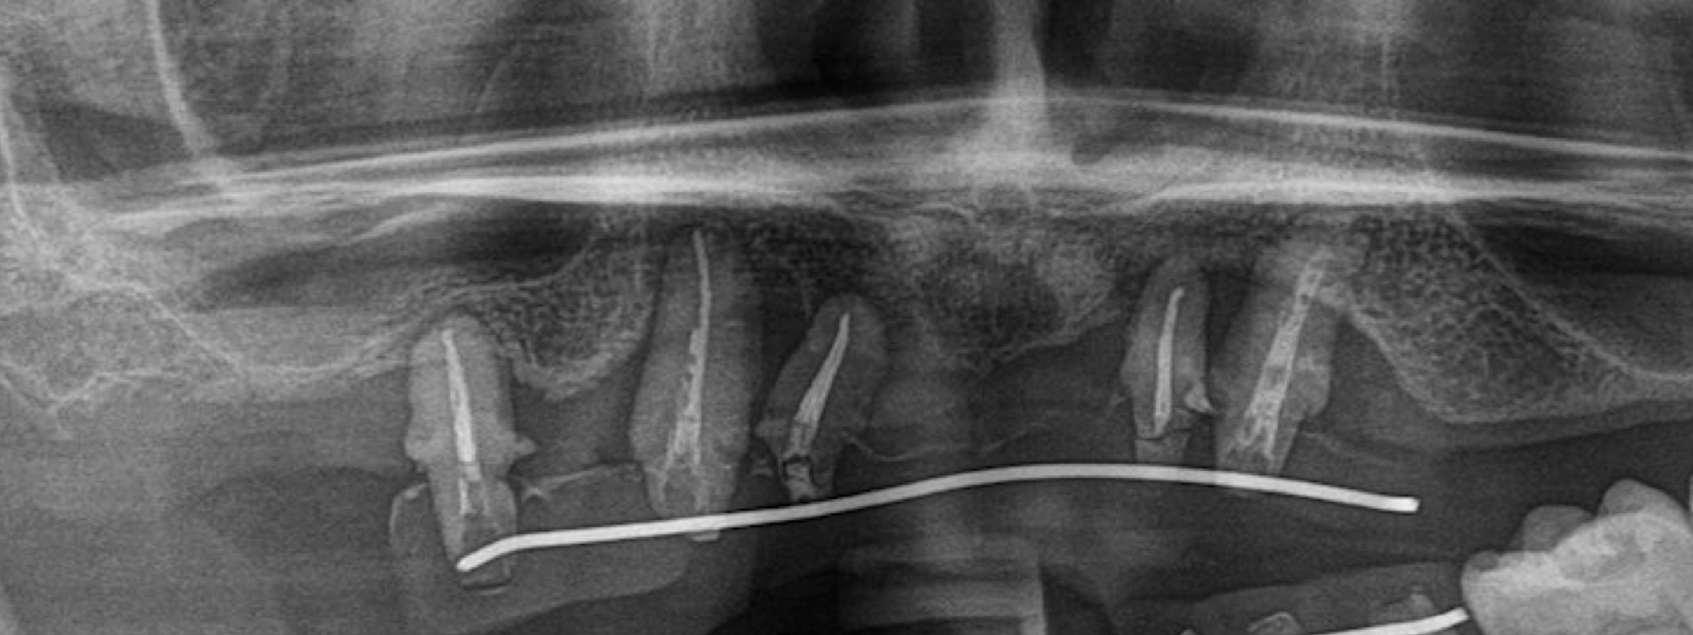

La Sfida del Tempo: Quando La Perdita Ossea Minaccia il Futuro del Sorriso

© Dr.Dr. Schmitz – FreeSmile